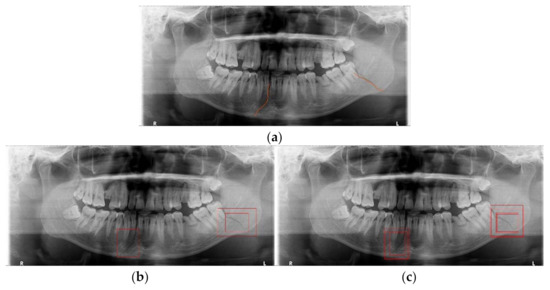

Mandibular fracture is one of the most frequent injuries in oral and maxillo-facial surgery. Radiologists diagnose mandibular fractures using panoramic radiography and cone-beam computed tomography (CBCT). Panoramic radiography is a conventional imaging modality, which is less complicated than CBCT. This paper proposes the [...] Read more.

Mandibular fracture is one of the most frequent injuries in oral and maxillo-facial surgery. Radiologists diagnose mandibular fractures using panoramic radiography and cone-beam computed tomography (CBCT). Panoramic radiography is a conventional imaging modality, which is less complicated than CBCT. This paper proposes the diagnosis method of mandibular fractures in a panoramic radiograph based on a deep learning system without the intervention of radiologists. The deep learning system used has a one-stage detection called you only look once (YOLO). To improve detection accuracy, panoramic radiographs as input images are augmented using gamma modulation, multi-bounding boxes, single-scale luminance adaptation transform, and multi-scale luminance adaptation transform methods. Our results showed better detection performance than the conventional method using YOLO-based deep learning. Hence, it will be helpful for radiologists to double-check the diagnosis of mandibular fractures. Full article

Show Figures